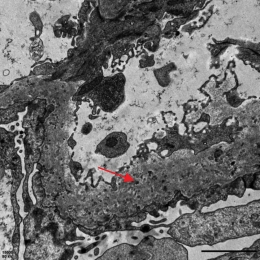

肾活检病理:全片共见约20个肾小球,其中约4个小球球性硬化,个别肾小球稍缺血皱缩,少部分肾小球节段有轻度系膜细胞增生或系膜基质增多,但毛细血管壁明显增厚、僵硬,毛细血管腔开放良好,未见袢坏死或新月体形成,PASM染色见毛细血管壁增厚,部分节段可见钉突和包裹(见图1)。肾小管上皮细胞变性坏死不明显,偶见个别小管萎缩,少数小管中有蛋白管型,间质偶见少量炎细胞浸润,间质纤维化轻微。免疫荧光检查:全片共见约10个肾小球,其中IgA(-),IgM(-),IgG(+),C1q(-),C3(±),Kappa(±),Lambda(±),弥漫性,球性,细颗粒样或线样以毛细血管壁沉积为主。电镜:少部分系膜区可见轻度系膜细胞增生和系膜基质增多,系膜区、内皮下和上皮下电子致密物不明显,内皮细胞胞质内见管网状包涵体,肾小球基底膜(glomerular basement membrane,GBM)明显增厚,基底膜内可见大量微球样膜样结构,足突明显融合(见图2)。肾小管间质未见明显电子致密物。

注:肾小球基底膜明显增厚,基底膜内可见大量微球样膜样结构(见红色箭头)